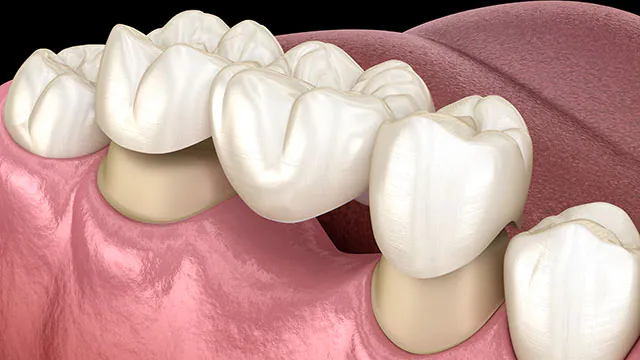

Dental bridges are used to replace one or more missing teeth. They consist of artificial teeth (pontics) that are anchored to adjacent natural teeth or dental implants. The supporting teeth, called abutments, are typically crowned to provide stability and support for the bridge. Dental bridges help restore the functionality and appearance of the smile.